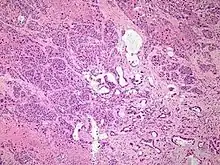

Histopathology

The most common form of pancreatic cancer (adenocarcinoma) is typically characterized by moderately to poorly differentiated glandular structures on microscopic examination. There is typically considerable desmoplasia or formation of a dense fibrous stroma or structural tissue consisting of a range of cell types (including myofibroblasts, macrophages, lymphocytes and mast cells) and deposited material (such as type I collagen and hyaluronic acid). This creates a tumor microenvironment that is short of blood vessels (hypovascular) and so of oxygen (tumor hypoxia).[2] It is thought that this prevents many chemotherapy drugs from reaching the tumor, as one factor making the cancer especially hard to treat.[2][3]

| Cancer type | Relative incidence[11] | Microscopy findings[11] | Micrograph | Immunohistochemistry markers[11] | Genetic alterations[11] |

|---|---|---|---|---|---|

| Pancreatic ductal adenocarcinoma (PDAC) | 90% | Glands and desmoplasia | ![]() | ||